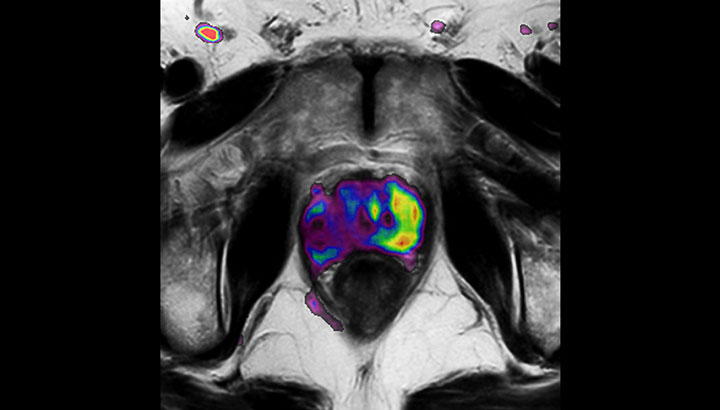

With its exceptional soft-tissue visualization capabilities and wide range of image contrasts, MRI has become a powerful tool to help more precisely define tumor boundaries. This is particularly important as it has been established that there is a high degree of uncertainty in target volume delineation, and it is even reported to represent the largest uncertainty in the entire radiotherapy process for most tumor sites**. Better visualization of the target area and nearby organs-at-risk is a key factor in enhancing target volume delineation. MRI’s expanding role also can be attributed to its functional imaging capabilities, which can inform both target characterization and treatment response.

Explore clinical cases that demonstrate the use of MRI for RT planning.